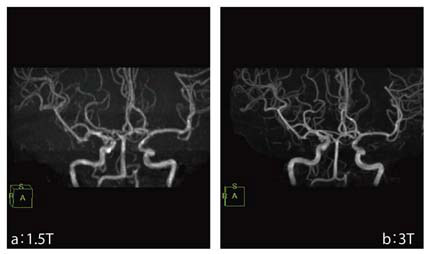

図2 3Tと1.5TにおけるTOF法を用いたMRAの比較

a:(1.5T)TR/TE 29/6.9,マトリックス256×256,NEX1,撮像時間 5分01秒

b:(3T)TR/TE 22/2.8,マトリックス384×224,NEX1,撮像時間 4分46秒